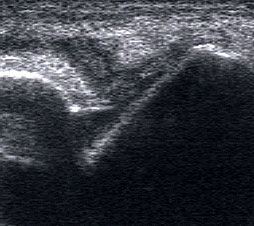

Tendopathien der Flexorensehnen

Dorsaler TS hinter dem Innenknöchel.

Abbildung 46

Lagerung: Rückenlage, Außendrehung des Beines.

Schnittführung: TS und LS hinter dem Innenknöchel beginnen und bis zum Os cuneiforme mediale fortführen.

Referenzstrukturen: Innenknöchel, Talus, Os naviculare, Os cuneiforme mediale, Sehnen der Mm tibialis posterior, flexor hallucis longus, flexor digitorum.

Befunde: Häufig betreffen die Pathologen die Tibialis-posterior-Sehne, die als erste Sehne hinter dem Innenknöchel zur Darstellung kommt. Halo-Phänomen und echoarme Verdickung bei akuter Tendinopathie, zunehmend inhomogen und echogen mit Kaliberschwankungen bis hin zu Teilrupturen bei Chronifizierung 5. Für die Erkennung von Teilrupturen sind TS in verschiedener Höhe besonders wichtig. Bei komplettem Riss mit Retraktion im LS Bild wie Spargelspitze mit umgebender Flüssigkeit oder Hämatom. Ein Os tibiale externum erscheint als echoreiche Struktur im Verlauf der Tibialis posterior Sehne mit dorsaler Schallauslöschung. Ein Os naviculare cornutum imponiert als starke Prominenz im Ansatzbereich der Tibialis posterior Sehne.